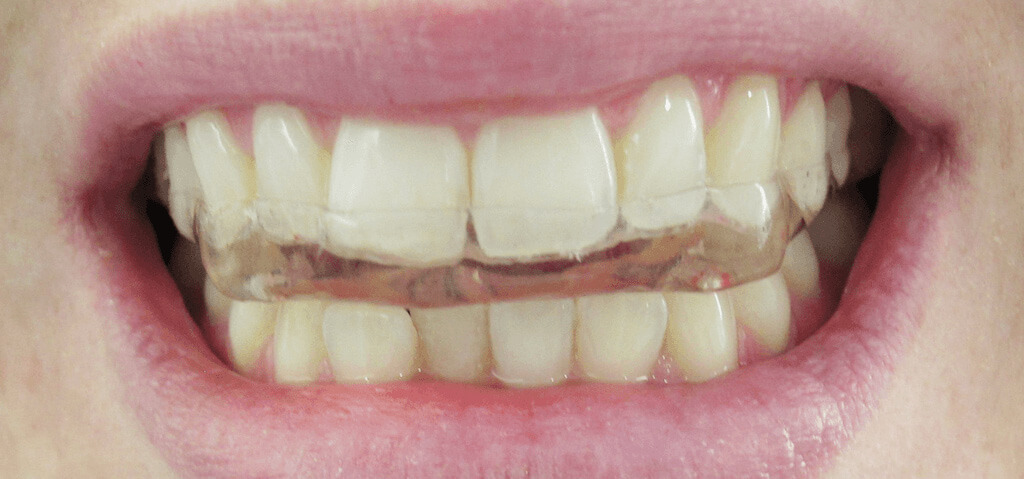

Plano de tratamento: Colocação de 4 implantes superiores e 2 implantes inferiores. Confeção de uma barra superior e colocação de 2 locators® na parte inferior. Confeção de uma prótese superior e outra inferior removível, com encaixes na barra e locators®.

A escolha deste plano de tratamento deve-se ao facto de o paciente querer uma solução total, mas não completamente fixa, uma vez que não tinha muita destreza manual para higienizar uma prótese fixa. Desta forma, conseguiu uma solução bastante retentiva (devido aos encaixes) mas que consegue remover para uma higienização correta.